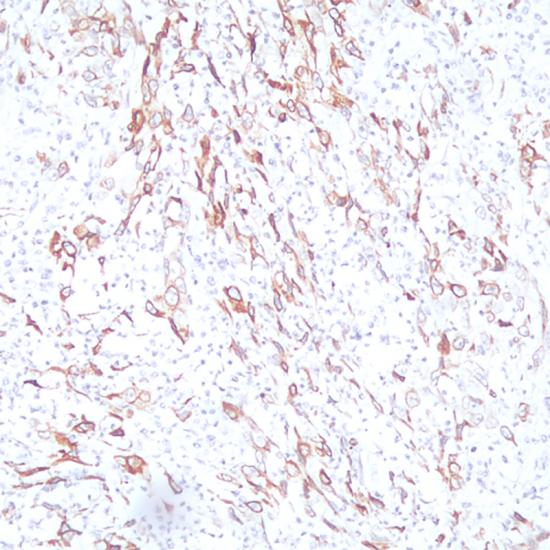

COX-2抗體試劑(免疫組織化學(xué))    閩廈械備20180198號

• 預(yù)處理:

熱修復(fù)

• 陽性部位:

細(xì)胞漿/細(xì)胞膜

• 陽性對照:

肺鱗癌

• 適用組織:

石蠟

• 免疫顯色試劑:

iVision?

• 產(chǎn)品編號:

AR0080

• 種屬來源:

兔單抗

• 克隆號:

SP21

環(huán)氧化物酶可以通過催化精氨琥珀酸合成環(huán)內(nèi)過氧化物而形成前列腺素,具有兩種異構(gòu)體形式:COX-1和COX-2,COX-2是—種誘導(dǎo)型酶。COX-2被認(rèn)為是免疫調(diào)節(jié)研究中的一個(gè)理想標(biāo)記物和 抗炎性疾病的治療靶標(biāo)。COX-2的表達(dá)或過表達(dá)與癌生成有關(guān)。在直腸癌、肺癌、食道癌、前列腺癌、乳腺癌和卵巢癌中均有表達(dá)。